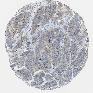

STOMACH CANCER - Protein expressioni

A mouse-over function shows sample information and annotation data. Click on an image to view it in a full screen mode. Samples can be filtered based on level of antibody staining by selecting one or several of the following categories: high, medium, low and not detected. The assay and annotation is described here.

Note that samples used for immunohistochemistry by the Human Protein Atlas do not correspond to samples in the TCGA dataset.

Antibody stainingi

Antibody staining in the annotated cell types in the current human tissue is reported as not detected, low, medium, or high, based on conventional immunohistochemistry profiling in selected tissues. This score is based on the combination of the staining intensity and fraction of stained cells.

Each image is clickable and will lead to virtual microscopy that enables deeper exploration of all samples and also displays staining intensity scores, fraction scores and subcellular localization as well as patient and tissue information for each sample.

Antibody HPA013994

Antibody HPA013995

Adenocarcinoma, NOS

Adenocarcinoma, High grade